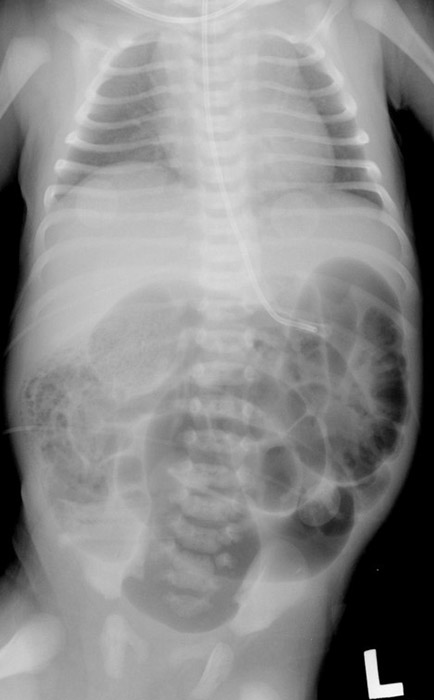

What is imperforate anus?

A congenital failure of the membrane between the rectum and anus to rupture.

Why does bowel obstruction occur in imperforate anus?

The rectum does not communicate with the anus.

How is imperforate anus categorized anatomically?

As high or low, depending on distance from the anus.

What is the earliest sign of imperforate anus?

Failure to pass meconium. (babies first stool)

What additional signs may be present with imperforate anus?

Abdominal distension and stool in urine or vagina.